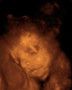

Krümmel bei der Nackenfaltenmessung, SSL 48,4 mm, man konnte schon richtig schön die Gesichtsform erkennen, vorallem die Stupsnase :-), Nackenfalte ist 1mm also unauffällig.